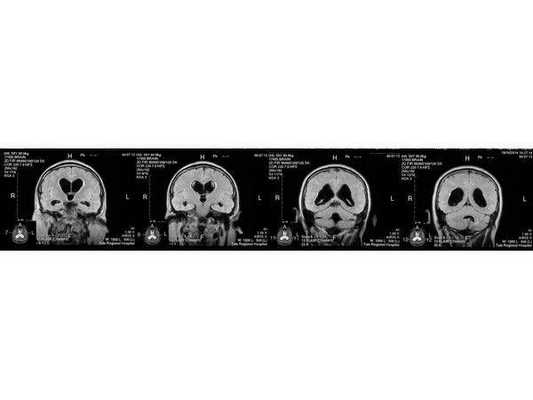

- МРТ в динамике показывает постепенное сужение желудочковой системы на 2 мм. Для сравнения представлены снимки МРТ от 14.05.2013 и от 16.10.2014.

МР-томограмма нормального головного мозга. Серым цветом изображено вещество мозга, белым - ликвор. Нормальная величина жидкостных пространств головного мозга (они щелевидны). Желудочки видны внутри мозга. Субарахноидальные пространства - белая кайма вокруг мозга.

МР-томограммы при внутричерепной гипертензии и гидроцефалии. Результат недостаточного лечения повышенного внутричерепного давления. Видно избыточное скопление ликвора внутри головного мозга (в виде бабочки) и снаружи мозга (широкая белая кайма). Объем мозгового вещества уменьшен - атрофия головного мозга от давления жидкостью.